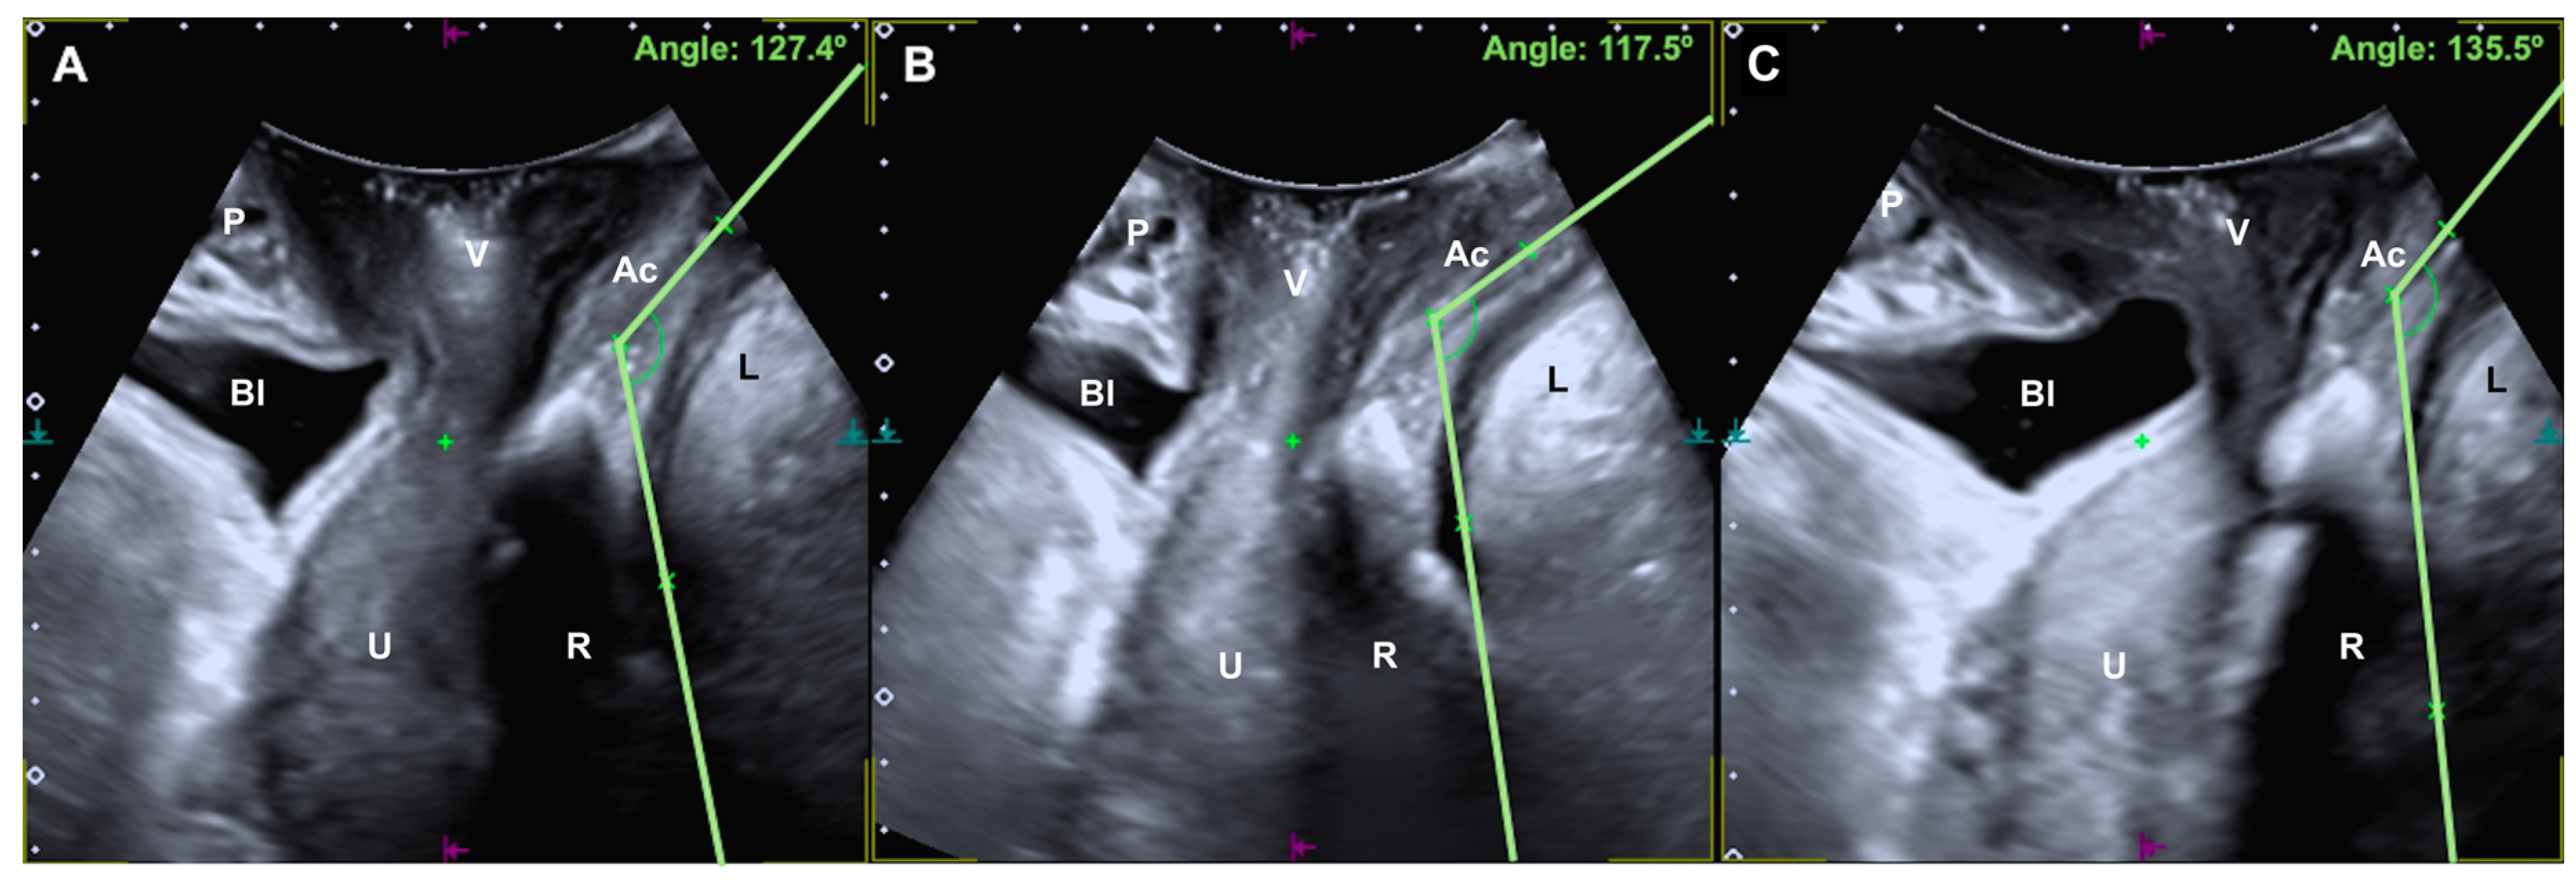

2.3. Ultrasound Assessment